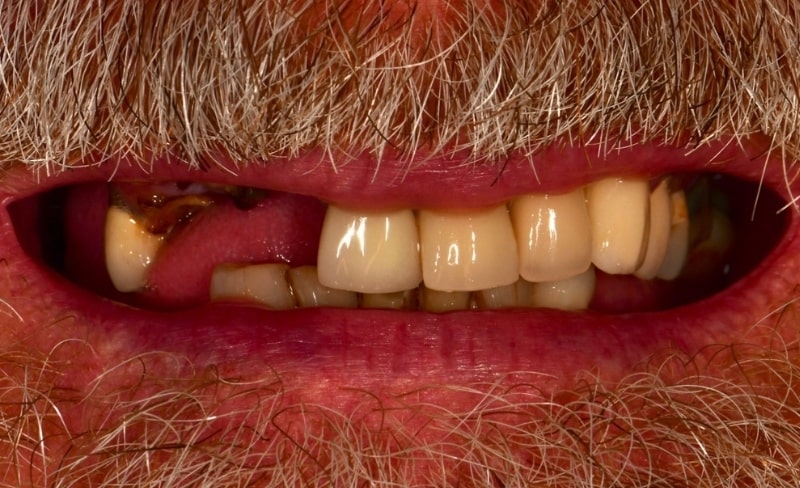

Upper and lower all-on-4 dental implants to restore function and aesthetics.